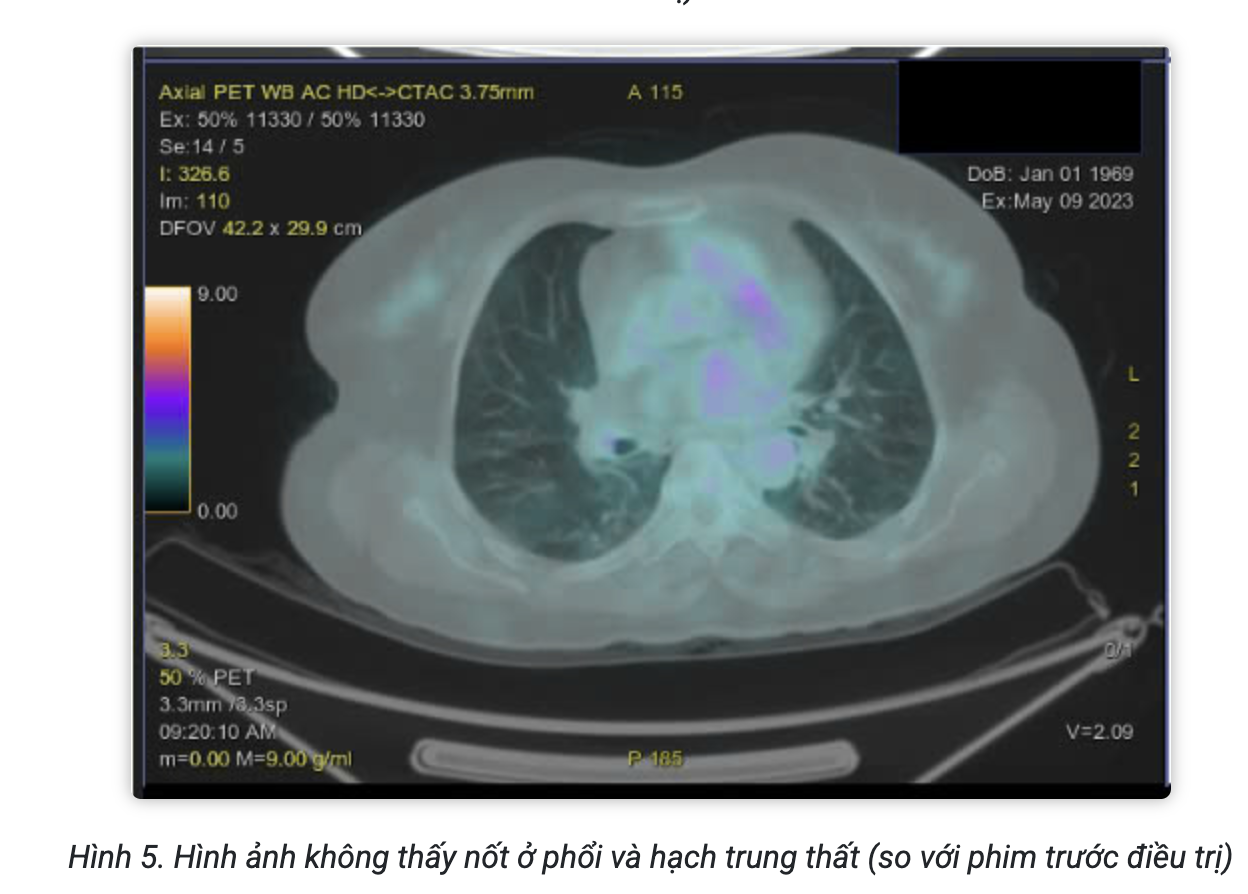

Sau điều trị 4 chu kỳ, bệnh nhân được chụp PET/CT đánh giá đáp ứng điều trị:

Kết luận:

- Không thấy hình ảnh tăng chuyển hóa ở tiểu khung

- Hình ảnh tăng chuyển hóa FDG lan tỏa ở tủy xương đốt sống ngực, thắt lưng, xương chậu 2 bên do phản ứng.

- Hình ảnh vài dải mờ và đám kính mờ phân bố rải rác nhu mô 2 phổi, không tăng chuyển hóa FDG.

Theo thang điểm 5-PS, bệnh nhân có đáp ứng là điểm 1 tại các tổn thương. Bệnh đáp ứng hoàn toàn trên PET/CT.